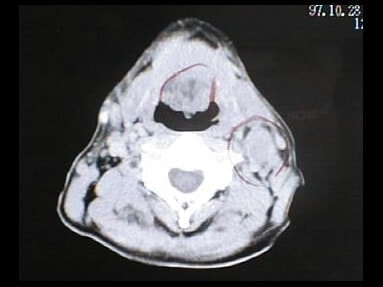

末期がん宣告時と末期がん消滅時の診断画像比較

ここでは、末期がんと宣告された時のCT&MRI画像と、その約3か月後の末期がん消滅時の画像を比較して頂けます。(写真左が「末期がん宣告時の画像」、写真右が「末期がん消滅後の画像」)

CT画像比較

中咽頭末期がんCT画像①

入院当時CT画像①

中咽頭末期がん消滅CT画像①

入院3か月後癌消滅CT画像①